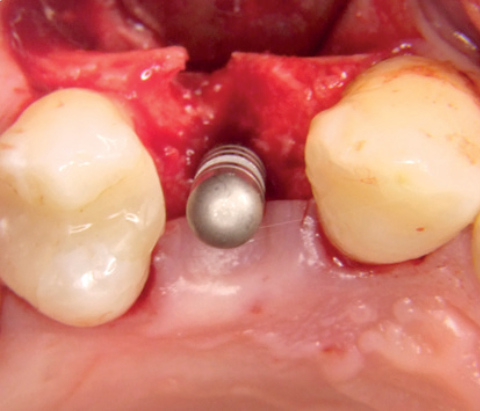

Laterale Augmentation im posterioren Unterkiefer

Prof. Božić

Kroatien

Augmentation eines Implantat-Dehiszenzdefekts mit „Sticky Bone“

Dr. Müller-Busch

Deutschland